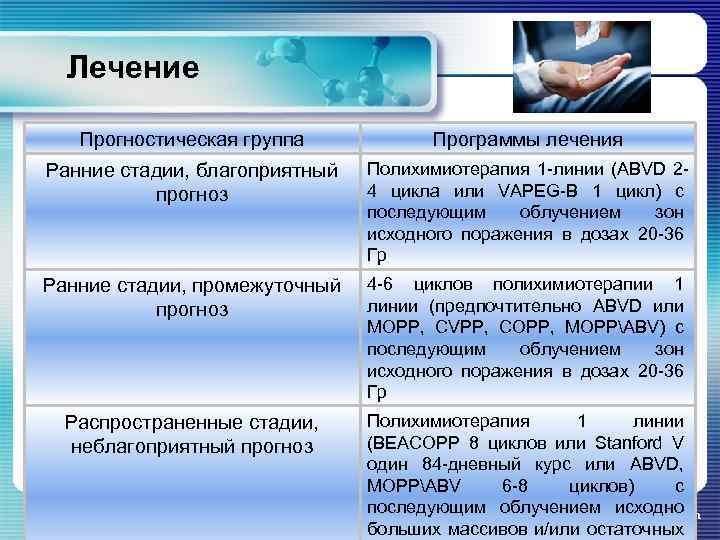

Лечение Прогностическая группа Программы лечения Ранние стадии, благоприятный прогноз Полихимиотерапия 1 -линии (ABVD 24 цикла или VAPEG-B 1 цикл) с последующим облучением зон исходного поражения в дозах 20 -36 Гр Ранние стадии, промежуточный прогноз 4 -6 циклов полихимиотерапии 1 линии (предпочтительно ABVD или MOPP, CVPP, COPP, MOPPABV) с последующим облучением зон исходного поражения в дозах 20 -36 Гр Распространенные стадии, неблагоприятный прогноз Полихимиотерапия 1 линии (BEACOPP 8 циклов или Stanford V один 84 -дневный курс или ABVD, MOPPABV 6 -8 циклов) с последующим облучением исходно www. themegallery. com больших массивов и/или остаточных

Лечение Прогностическая группа Программы лечения Ранние стадии, благоприятный прогноз Полихимиотерапия 1 -линии (ABVD 24 цикла или VAPEG-B 1 цикл) с последующим облучением зон исходного поражения в дозах 20 -36 Гр Ранние стадии, промежуточный прогноз 4 -6 циклов полихимиотерапии 1 линии (предпочтительно ABVD или MOPP, CVPP, COPP, MOPPABV) с последующим облучением зон исходного поражения в дозах 20 -36 Гр Распространенные стадии, неблагоприятный прогноз Полихимиотерапия 1 линии (BEACOPP 8 циклов или Stanford V один 84 -дневный курс или ABVD, MOPPABV 6 -8 циклов) с последующим облучением исходно www. themegallery. com больших массивов и/или остаточных